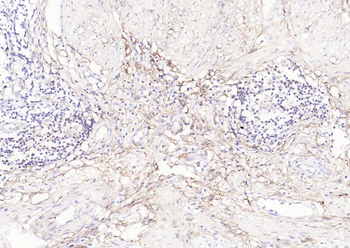

IHC staining of FFPE human tonsil tissue with CD73 antibody (clone NT5E/2545). HIER: boil tissue sections in pH9 10mM Tris with 1mM EDTA for 10-20 min and allow to cool before testing.

IHC staining of FFPE human tonsil tissue with CD73 antibody (clone NT5E/2545). HIER: boil tissue sections in pH9 10mM Tris with 1mM EDTA for 10-20 min and allow to cool before testing.